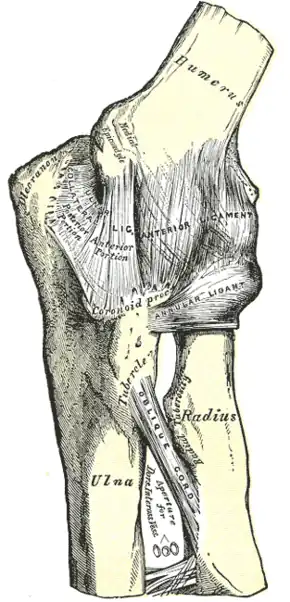

Left elbow-joint, showing anterior and ulnar collateral ligaments.

Left elbow-joint, showing anterior and ulnar collateral ligaments. -